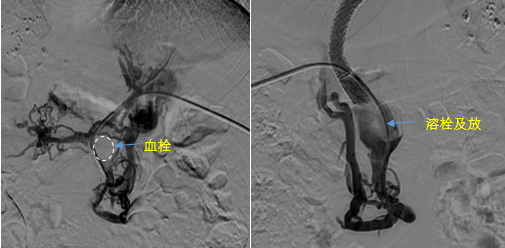

• 血栓攔路,如何破局——罕見巨大門靜脈血栓TIPS手術(shù)實(shí)錄

血栓攔路,如何破局——罕見巨大門靜脈血栓TIPS手術(shù)實(shí)錄

日前,西安國(guó)際醫(yī)學(xué)中心醫(yī)院消化病醫(yī)院為一位罕見巨大門靜脈血栓患者行TIPS手術(shù)。將患者體內(nèi)的“定時(shí)炸彈”拆除。9月份的一天,李女士晚飯后發(fā)覺惡心,嘔吐出鮮紅色的血塊,隨即又出現(xiàn)了黑便。在醫(yī)院檢查發(fā)現(xiàn)是食管胃底靜脈曲張破裂出血。……